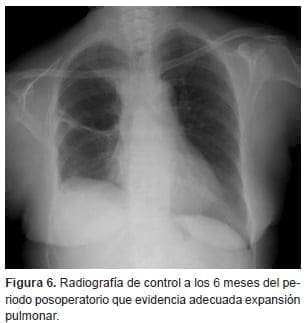

En la fibrobroncoscopia de control, la sutura estaba íntegra con adecuada cicatrización y había algunos tapones mucosos. La evolución continuó hacia la mejoría, pudiendo ser dada de alta a los 17 días del periodo posoperatorio. Los hallazgos fueron normales hasta el último control realizado (figura 6).